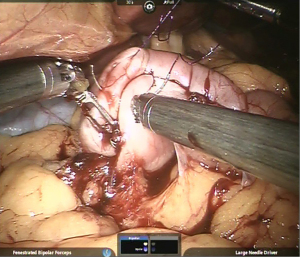

Gastro-jejunal anastomosis

Using barbed suture, imbrication of vertical limb of gastric pouch is continued as fourth layer of Gastro-Jejunostomy (Figure 10).

Gastrostomy & Enterotomy made using Monopolar hook/harmonic shears and stoma widened using harmonic shears in R2 creating a stoma length of 2–2.5 cm approximately (Figure 11).

Using a new barbed suture, third layer (posteriorly) started from left side, towards right side. The same suture is reversed at the opposite end (right) to form the 2nd layer of anastomosis (anteriorly).

Anterior-most layer completed using another barbed suture thus completing the anastomosis (Figure 12).